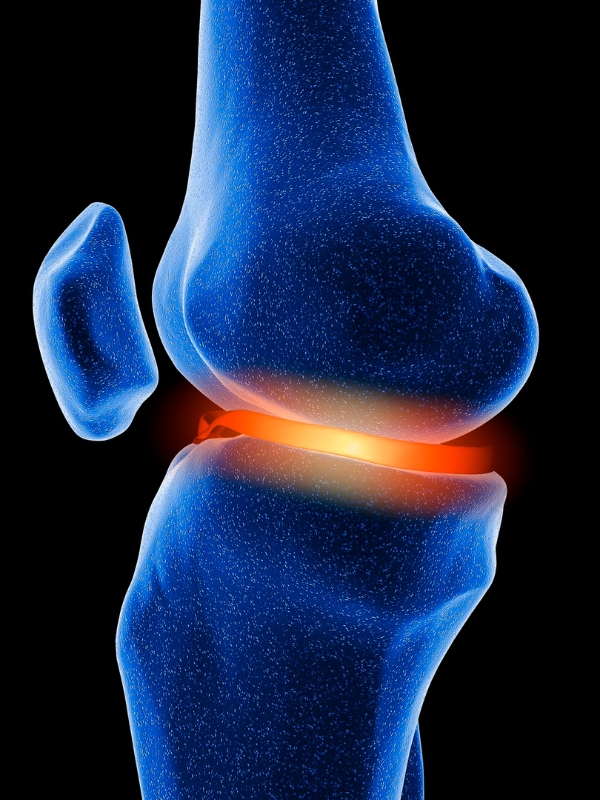

La Medicina Rigenerativa impiega cellule del paziente stesso per trattare patologie articolari, in particolare quelle che colpiscono spalla, ginocchio e anca, con focus su cartilagine e tendini. La cartilagine, essendo priva di vascolarizzazione, ha una scarsa capacità di autoriparazione; per questo motivo le sue lesioni possono evolvere in artrosi, causando dolore e limitazioni motorie.

PRP (Plasma Ricco di Piastrine): si ottiene dal sangue del paziente, viene centrifugato per isolare un siero ricco di piastrine, che viene iniettato nell’articolazione. Questo porta un’elevata concentrazione di fattori di crescita, riducendo dolore e infiammazione e stimolando la riparazione tissutale.

Cellule Mesenchimali: derivano da tessuto adiposo o midollo osseo del paziente. Hanno proprietà antinfiammatorie e immunomodulatorie e sono capaci di migrare verso i tessuti danneggiati, stimolando la rigenerazione della cartilagine e migliorando la qualità del liquido sinoviale. Il risultato è una riduzione dei sintomi e un rallentamento del decorso dell’artrosi.